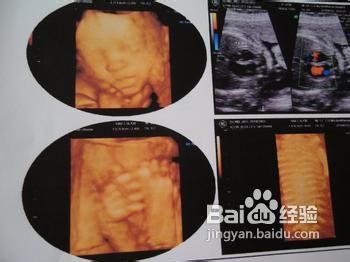

1、 胎儿超声心动图检查的适应症年龄大于35岁的高龄孕妇;既往有异常妊娠史,如胎死宫内,流产、羊水过多或羊水过少等;怀孕早期服用药物,如yang化锂,大lun丁等;孕期曾接触致畸物质;各种类型tang尿病、结缔组织病、感染xing疾病。

2、 胎儿因素心脏以外器官畸形、染色体异常、非免疫xing水肿、羊水过多、透明层厚度增加、双胎妊娠等。家族因素。

3、 据报道先天性心脏病占我国出生婴儿的8%-12%,意味着我国每年有12万-20万的先天性心脏病患儿出生,其中复杂的、目前治疗手段尚不能达到良好治疗效果的或易出生后早期死亡的先心病约占20%,是新生儿及儿童期的主要死亡原因之一。